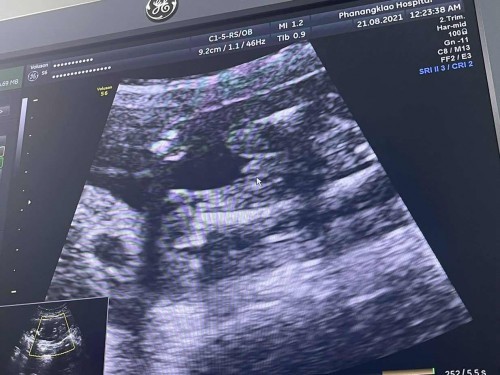

ช่วยดูเพศน้องหน่อยจ้า

แม่แม่ว่าในภาพน้องเป็นผู้หญิงหรือว่าผู้ชายคะตอนอันตสาวอายุครรภ์ 17 สัปดาห์ค่ะ #ขอบคุณสำหรับคำตอบค่ะ

เหมือนแท่งๆเลยแม่ รอหมอคอนเฟิร์มนะคะ